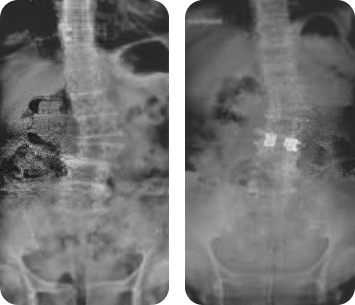

Клинический пример

Применение кейджей VariAn ExpandableTM при хирургическом лечении спондилолистеза и сколиотической деформации.

- Пациент:

- Женщина, 51 год.

- Диагноз:

- Дегенеративный спондилолистез поясничного отдела позвоночника со стенозом позвоночного канала.

- Лечение:

- Выполнена редукция и фиксация кейдами VariAn ExpandableTM. Контрольные рентгенограммы выполнены через 1 и 2 года после операции.